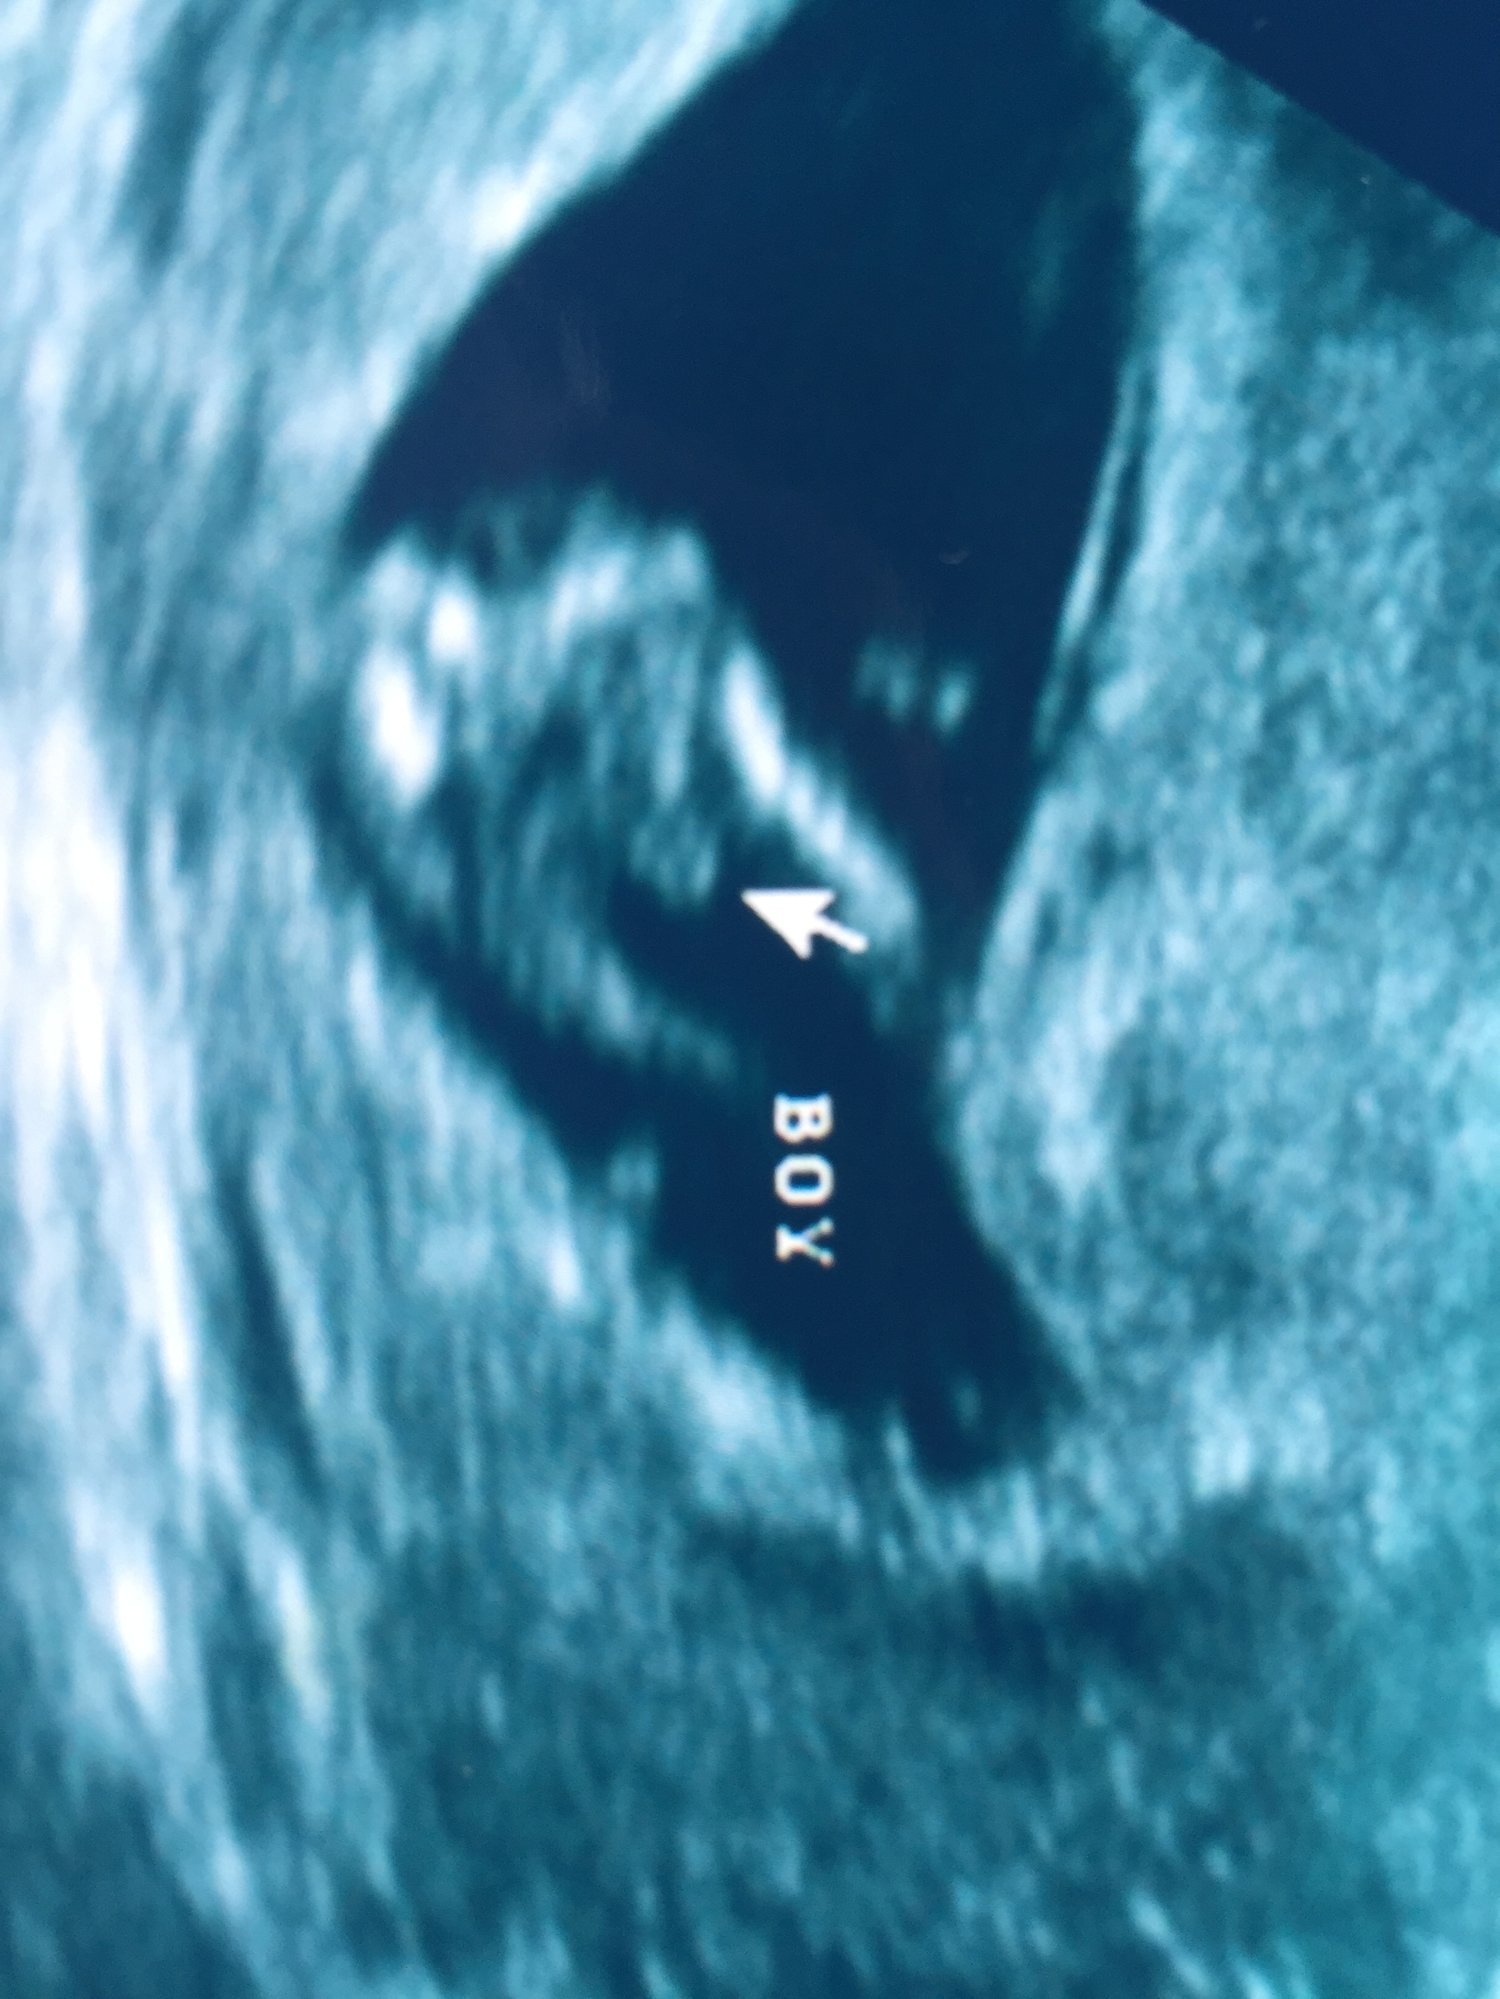

Baby Boy due 04/07/17